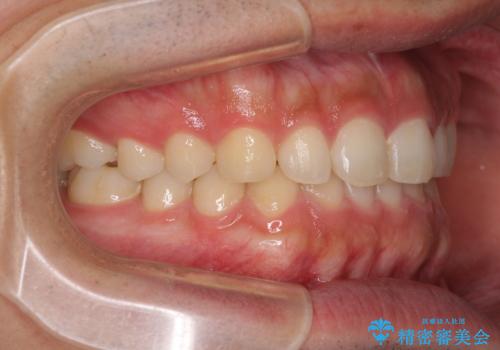

インビザラインによる、すきっ歯の改善

- 前歯がすきっ歯であることを気にして来院された患者様です。

下の前歯がほとんど隠れてしまうくらいの深い咬み合わせであったので、インビザラインを用いて、咬み合わせの高さを改善しながら隙間を閉じていくこととしました。

咬合力で上の前歯が前方に押し出されるようにして隙間ができていましたが、矯正治療により全て閉じることができました。

深い咬み合わせも多少改善され、隙間も閉じたことで、前方に出ていた前歯が引っ込んだため、口も閉じやすくなったとのことでした。